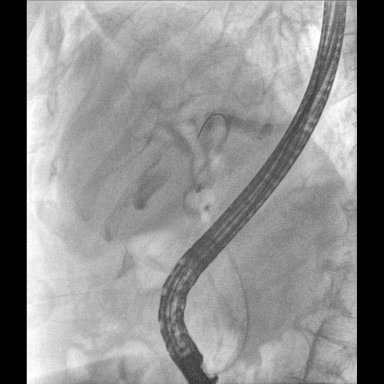

具備血管造影及數(shù)字減影(DSA)、路徑圖(Road-map)、透視、攝影等功能。 廣泛適用于介入科、血管外科、腫瘤科、消化內(nèi)科及骨科等多個臨床科室,典型應(yīng)用包括:TACE(肝腫瘤栓塞與化療灌注術(shù))、心臟起搏器置入術(shù)、四肢動脈造影術(shù)、下肢靜脈濾器置入術(shù)、ERCP(經(jīng)內(nèi)鏡逆行胰膽管造影術(shù))等。

預(yù)留高壓注射器聯(lián)動接口,C形臂開始透視時,高壓注射器自動注入造影劑,提高術(shù)中造影減影效率,減少醫(yī)師手推造影劑所受到的輻射暴露劑量。